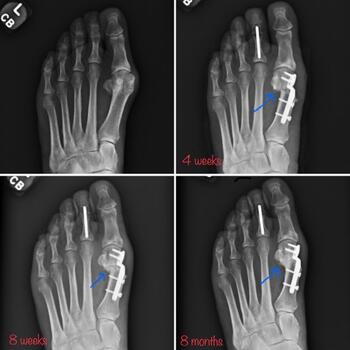

The surgeon may shift the capital fragment as much as necessary as long as there is some contact maintained between the metatarsal shaft and the head. It is possible to plan the amount of translation necessary on the preoperative X-ray, based on the position of the fibular sesamoid. In our experience, the lateral cortex of the metatarsal head should end up in a position just lateral to the fibular sesamoid on the preoperative X-ray. The gap between the lateral metatarsal head and metatarsal shaft will consolidate over time (see sixth and seventh photos above). A multitude of advanced options for fixation exist, including, but not limited to headless compression implants (see seventh and ninth photos above) and plate-intramedullary hybrid devices (see sixth photo above). Intramedullary devices do require a slightly larger incision for appropriate placement.

We have found success with immediate protected weight bearing in a short CAM walker boot. The lack of violation of the first MPJ capsule is the most advantageous portion of this procedure, as we avoid fibrosis or adhesions from the arthrotomy. We advise aggressive range of motion to tolerance daily for the first six weeks postoperatively. At four weeks, transition to a surgical shoe/may take place, and at six weeks, transition to supportive sneaker with accommodative insert. We typically obtain radiographs at four and eight weeks postoperatively. It is unnecessary to see bone consolidation before transition to sneaker as this secondary callus formation may lag behind the clinical union. We rely on patient symptoms and pain on palpation at the osteotomy site.